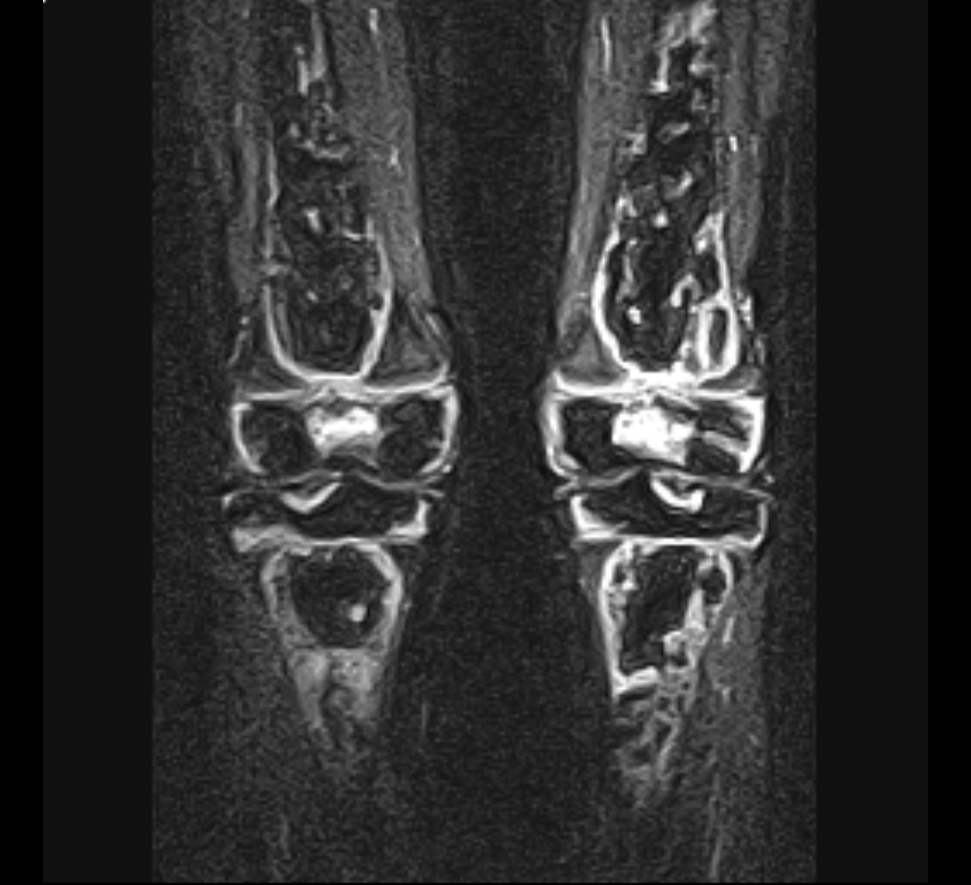

흔히 연골주사로도 불리는 히알루론산 주사는 관절내 활액의 점성과 탄성을 높게 해준다.

통증을 감소시키는 효과는 주사 후 1~3주 후에 나타나지만,

효과는 개인차에 따라 보통 6개월에서 1년 정도 효과가 지속된다.

대개 주 1회 시행하며, 3~5회 투여한다.